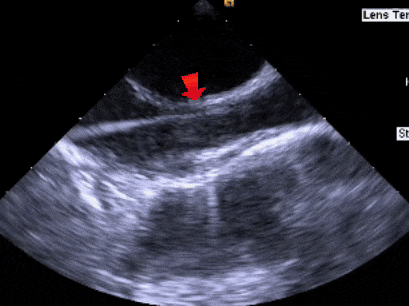

1、内脏正位,心房正位,心室右袢,各房室内径正常。房间隔可见封堵器回声,未见分流。右肺静脉流速0.59m/s,上腔静脉流速0.53m/s。

ASD封堵术后,未见分流